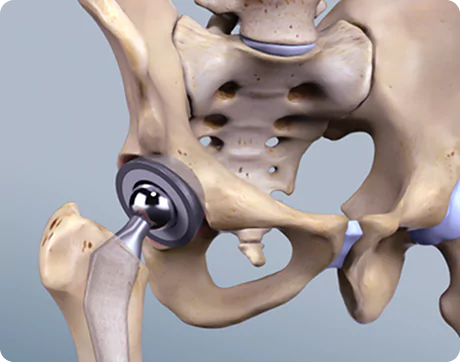

What Is Spine Surgery?

Spine surgery is a medical intervention aimed at treating conditions that affect the spinal column and spinal nerves. It becomes necessary when conservative treatments such as physiotherapy, medications, or injections fail to relieve persistent symptoms like chronic back pain, sciatica, or nerve compression.

The spine is a complex structure composed of vertebrae, discs, nerves, and ligaments. Problems in any of these areas can lead to severe pain, restricted movement, or neurological symptoms. Spine surgery helps to correct structural abnormalities, relieve pressure on spinal nerves, stabilise the spine, and restore function.